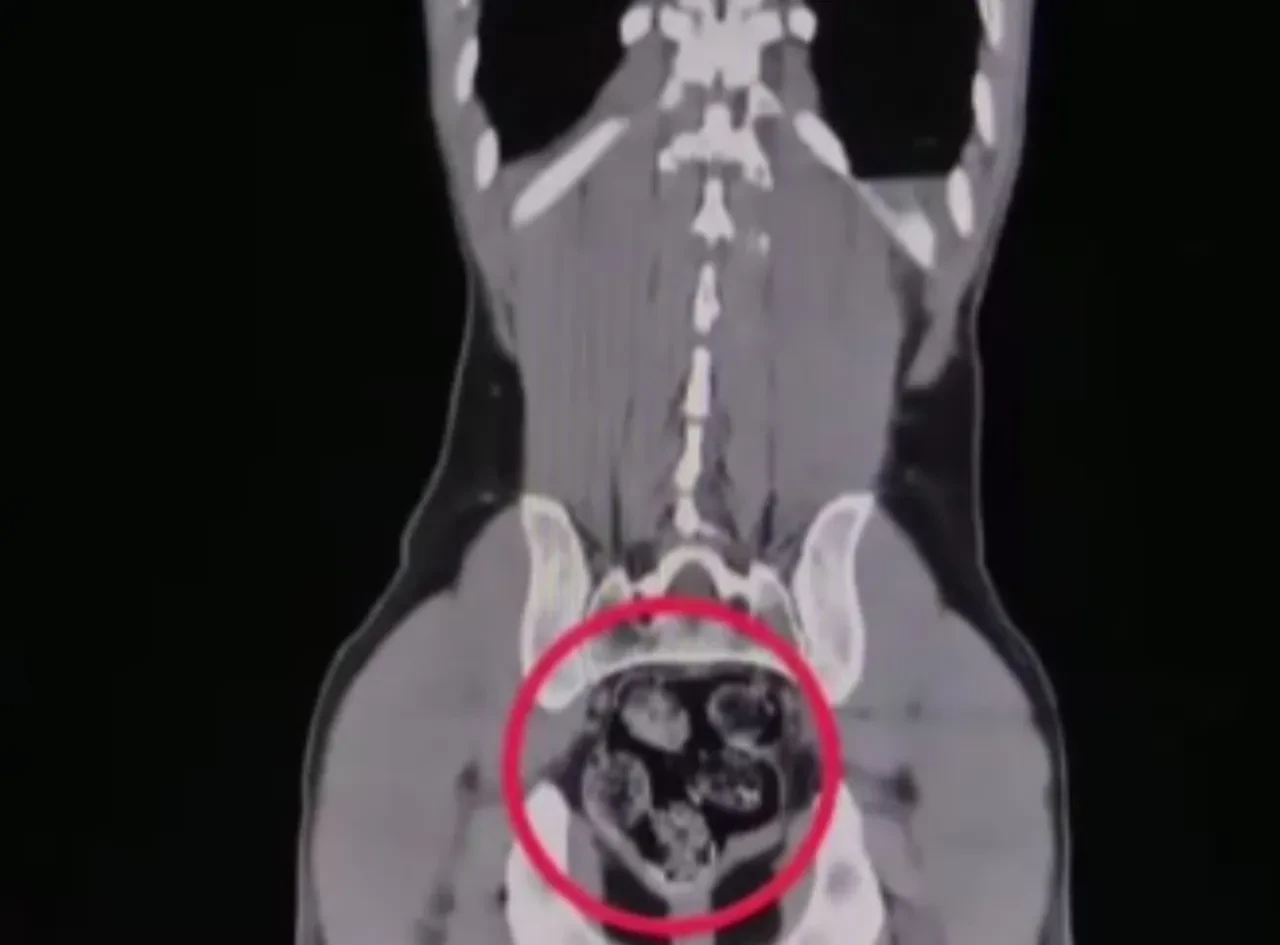

Düzenlenen operasyonda, İran uyruklu kuryeler gözaltına alındı. İl Emniyet Müdürlüğü'ne getirilen ve durumundan şüphelenilen kuryelerden Shekarbaghanı, detaylı arama için Kars Harakani Devlet Hastanesi'ne götürüldü. Hastanede yapılan emar ve röntgen kontrollerinde şüphelinin makatında cisim olduğu belirlendi.

Yapılan cerrahi müdahalede, şüphelinin makatından 7 parça halinde 203,02 gram metamfetamin çıkarıldı. Gözaltına alınan şüpheliler, emniyetteki sorgusunun ardından 'uyuşturucu veya uyarıcı madde ticareti yapma veya sağlama' suçundan adliyeye sevk edildi. Mahkemeye çıkarılan şüpheliler, tutuklanarak cezaevine gönderildi.